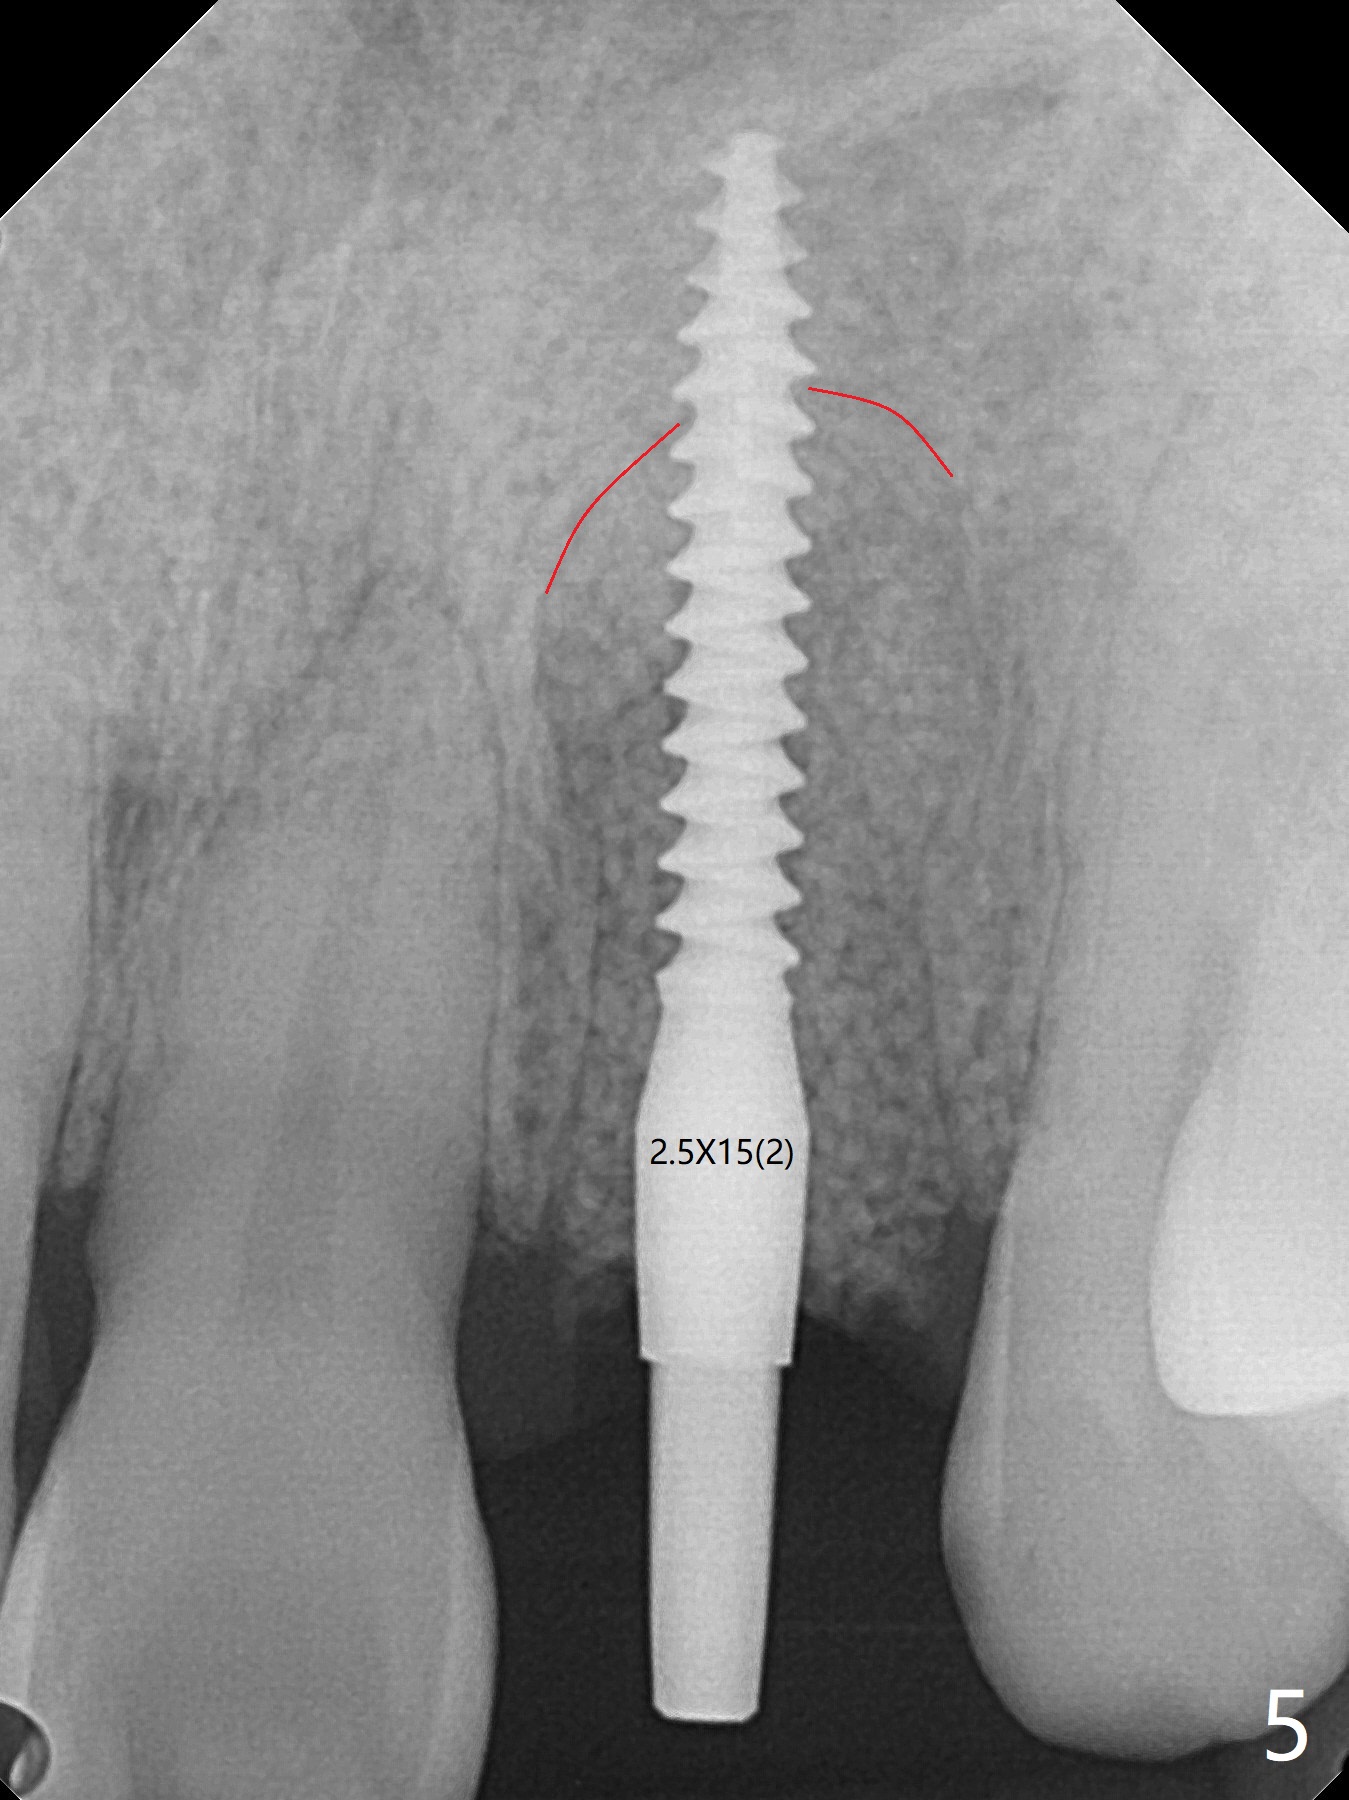

病人回来带来瘘道(图一),不过不会增加难度,病牙去除,它便自动消失。尽管颊侧骨壁完全失去,颊侧牙龈仍丰满(图二),为什么呢?第一,因为粗大牙根存在,第二两旁牙齿,牙槽骨撑着帐篷(侧切牙颊侧牙龈),第三,牙冠。为了防止术后牙龈塌陷,尽量不切开,即刻放置植体(牙根);由于前牙缘故,这次植体不能很大,所以植骨必须过度(over grafting),最后即刻制作临时牙冠,撑住牙龈。这就是所谓每个人进入角色。这个牙根有一种先天性畸形:dens in dent (图三(腭侧观):箭头)。尽管腭侧牙根畸形,腭侧骨壁吸收临床上并不严重,所以钻洞仍偏腭侧。当预定最后钻头还在钻洞时,填入大量粘性骨块(图四:*),细长植体还没有完全卡入鼻底(图五),最后好像可以(图六,七)。植体,骨粉入位(图八),最后临时牙冠出场(图九)。尽管植体小,术后一周临时牙冠仍然可以维持牙龈原有形状(emergency profile,图十:箭头(*:树脂强化牙冠固定))。图十一以不同角度显示瘘道缩小。术后三周取出有些松动的临时牙冠,骨粉虽然还没有被肉芽组织整合,但是显得正常,周围牙龈健康(图十二)。术后4个月牙龈形态正常(图十三),没有触痛;颊侧骨板轻度凹陷(图十四);骨粉仍在原位(图十五)。术后7个月骨粉仍在原位(图十五,十六,但是冠部密度减低(可能骨粉流失,需要牙周或者树脂敷料保护)),没有螺纹暴露。但是牙冠边缘暴露,说明牙龈收缩(图十七,与图十三对比),颊侧骨板仍塌陷(图十八)。插入龈线取得多个目的:修整基台边缘,取模,颊侧牙龈推向颊侧,有利于即将衬里牙冠龈缘进入龈下(图十九)。取模后牙冠边缘(图二十:<)衬里,然后修整,变窄,以便插入龈下,促进颊侧牙龈下降(图二十一,二十二)。术后8个月牙冠粘固前牙龈健康(图二十七,八),牙冠(图二十九)固位后,病人满意(图三十),咬合调整(图三十一),注意腭侧粘固粉流出通道(<)。